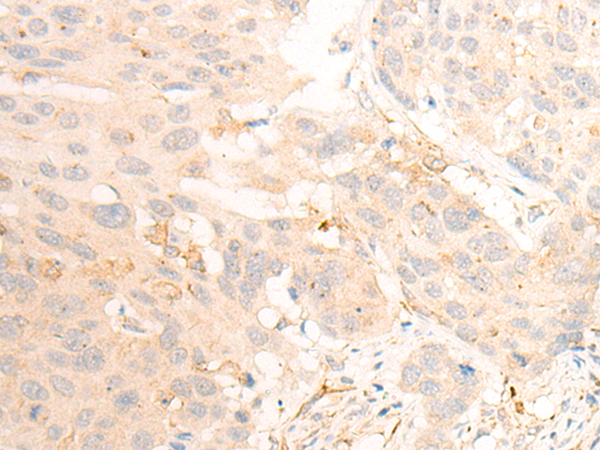

分类: 科研抗体货号: P13181别名: NOP132; C9orf34; bA62C3.3; bA62C3.4应用: IHC反应种属: Human